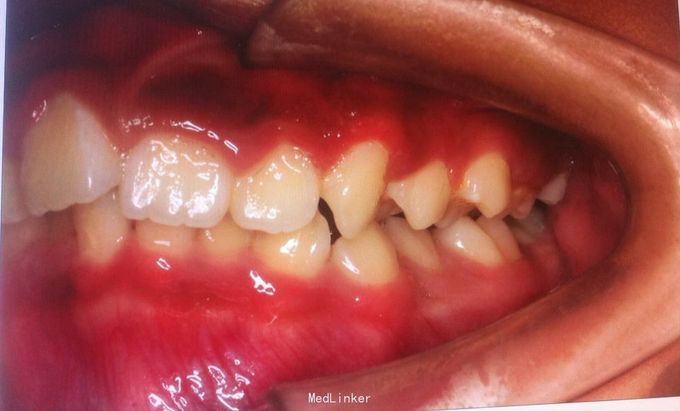

恒牙期 25正锁合 磨牙中性关系 前牙一度深覆盖深覆合 牙列拥挤 张口型异常

安氏一类 不拔牙矫治,直丝弓矫治器,排齐整平上下牙列,治疗后前牙覆合覆盖正常,磨牙中性关系,维持现有面型

面型略凸,若需改善面型,需在治疗中拔除四颗双尖牙